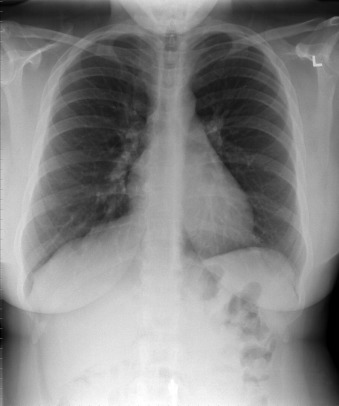

A patent foramen ovale is present in 25% to 30% of the adult population ( Figs. 18-1 to 18-4 ). Any magnitude of shunting across it in normal circumstances is undetectable radiographically. Percutaneous patent foramen ovale closure devices are fairly commonly inserted and are radiographically evident.